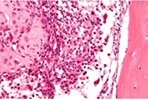

Upon microscopy, tumefaction is significantly cellular and composed of sheets of spherical to polyhedral chondroblastic cells imbued with abundant, eosinophilic cytoplasm and well demarcated cellular perimeter. Intracytoplasmic glycogen granules are evident. Nuclei appear elliptical, hyper-lobulated and demonstrate nuclear grooves. Nuclear atypia appears insignificant 1, 2.

Focal aggregates of spindle-shaped cells may be enunciated. Peri-cellular zones of ‘lace-like’ or ‘chicken wire’ calcification appear intermingled with degenerative chondroblasts. Eosinophilic foci of chondroid matrix are invariably discerned 1, 2.

Focal mitotic activity, necrosis and osteoclast-like giant cells may be commingled with cellular zones. Besides, aneurysmal bone cyst-like modifications are commonly observed 1, 2.

Figure 1.Chondroblastoma demonstrating round to oval chondroblastic cells with abundant, eosinophilic cytoplasm and vesicular grooved nuclei encompassed within a myxochondroid matrix5.

Figure 2.Chondroblastoma delineating aggregates of polyhedral chondroblastic cells with angulated, abundant, eosinophilic cytoplasm and vesicular nuclei enmeshed within a chondomyxomatous matrix6.